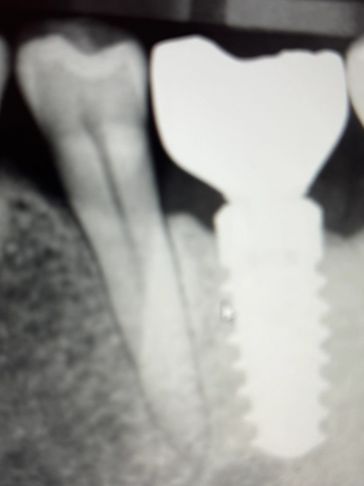

If a tooth is too badly decayed, fractured or the infection is too large, a root canal is not possible. At this point , an extraction and bone graft is required and a dental implant can be placed. Success of implants is between 90-95 % . it takes approximately 1 year from extraction , implant and final crown placement. You would ex

If a tooth is too badly decayed, fractured or the infection is too large, a root canal is not possible. At this point , an extraction and bone graft is required and a dental implant can be placed. Success of implants is between 90-95 % . it takes approximately 1 year from extraction , implant and final crown placement. You would expect for extraction, bone graft, and implant with final crown to cost between $2500 and $3000 dollars.